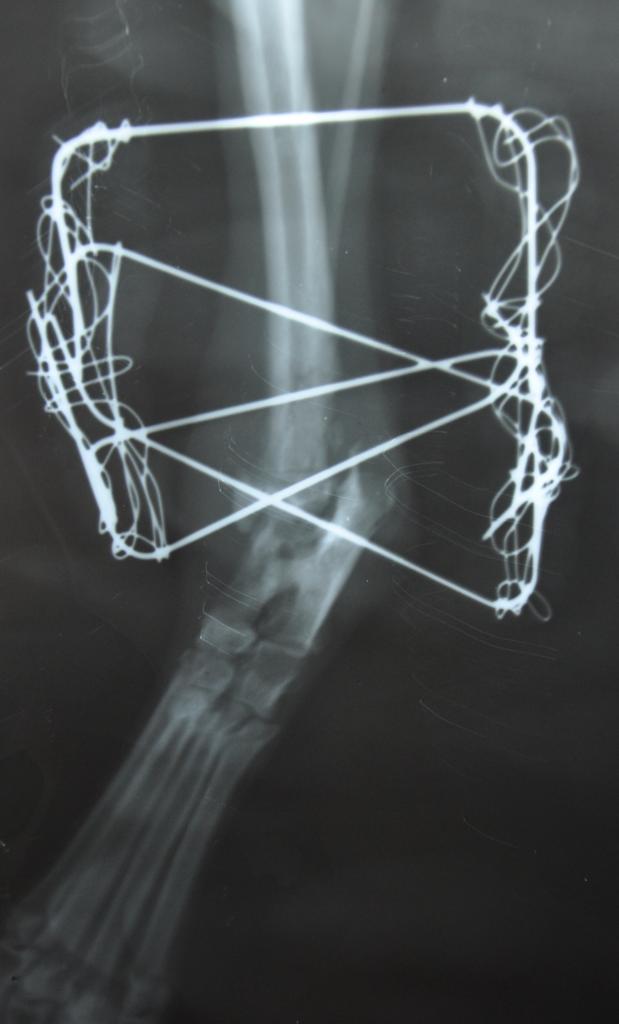

По умолчанию Новые фоточки Люсси) Бубочка такая, видно, что ей уже лучше)))

Нажмите на изображение для увеличения

Название: HPH9BzpOPR4.jpg

Просмотров: 6

Размер:	40.4 Кб

ID:	9736025Нажмите на изображение для увеличения

Название: fT-qxHQVlwE.jpg

Просмотров: 5

Размер:	28.7 Кб

ID:	9736037Нажмите на изображение для увеличения

Название: EWkvcVh6qG0.jpg

Размер:	29.0 Кб

ID:	9736035Нажмите на изображение для увеличения

Название: DSC_0004.jpg

Просмотров: 7

Размер:	42.7 Кб

ID:	9736034Нажмите на изображение для увеличения

Название: DSC_0002.jpg

Просмотров: 8

Размер:	69.8 Кб

ID:	9736033Нажмите на изображение для увеличения

Название: cdlqAnP_tOU.jpg

Просмотров: 11

Размер:	29.8 Кб

ID:	9736032Нажмите на изображение для увеличения

Название: a8C1t8gi0pY (1).jpg

Размер:	36.7 Кб

ID:	9736031Нажмите на изображение для увеличения

Название: a_iGviQeBcg.jpg

Размер:	35.7 Кб

ID:	9736030Нажмите на изображение для увеличения

Название: 7z2asyPpXnY.jpg

Размер:	39.6 Кб

ID:	9736029Нажмите на изображение для увеличения

Название: 1n1bDFUmOcg.jpg

Просмотров: 10

Размер:	38.9 Кб

ID:	9736028Нажмите на изображение для увеличения

Название: yGq2nB943pA.jpg

Размер:	22.7 Кб

ID:	9736027Нажмите на изображение для увеличения

Название: MDdKxYNxINE.jpg

Просмотров: 4

Размер:	33.0 Кб

ID:	9736026Нажмите на изображение для увеличения

Название: GE39Siht5lA.jpg

Размер:	26.8 Кб

ID:	9736038

Всем привет от Люсеньки! Она большой молодец,уже пытается становиться на лапку. Заживдение идет хорошо!!!! Завтра ,опять ,к ней поеду,еду завезу.

Девочки, спасибо за новости. Очень рада за Люси. Спасибо врачу за золотые руки. Видно , что барышня оживает. Очень надеюсь, что уйдут и внутренние проблемы в косточках.